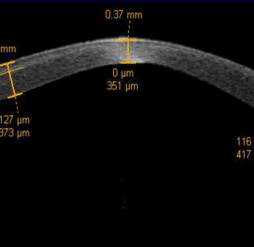

Ectasie cornéenne